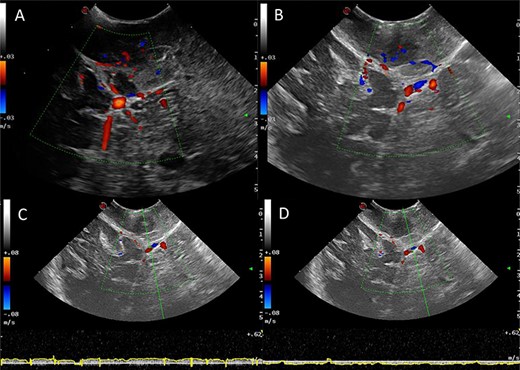

Ultrasound (B-mode) was used to identify the tumour margins, tentorium and venous structures (Fig. 2). Combined with the B-mode, Doppler ultrasound (US) was employed to assess the presence and direction of flow in the right transverse sinus, torcula and superior sagittal sinus. There was presence of blood flow in all these dural venous sinuses, however, the flow within the straight sinus was only unidirectional towards the torcula from the vein of Galen and from the tentorium tributary veins. The unique feature of the intracranial venous sinuses is that blood flow is bi-directional as they lack valves. Hence, this finding suggests there was a degree of venous insufficiency due to obstruction of the venous sinuses engulfed by the meningioma (Fig. 2).

IoUS initial assessment; (A) B-mode image of the surgical field; 1, supratentorial tumour; 2, infratentorial tumour; 3, tentorium; 4, straight sinus; 5, contralateral occipital lobe; 6, falx; (B) triplex Doppler of the straight sinus: combined 2D image with overlay of the colour and pulse wave Doppler demonstrating unidirectional flow from the vein of Galen and the tributary veins of the tentorium.